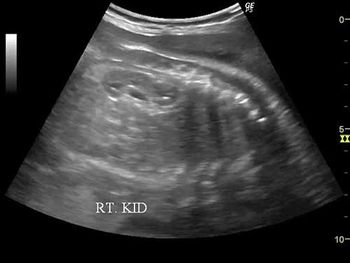

Challenge your diagnostic skills with these images of fetal kidneys.

Challenge your diagnostic skills: See anything out of the ordinary in the kidneys of this third trimester fetus?